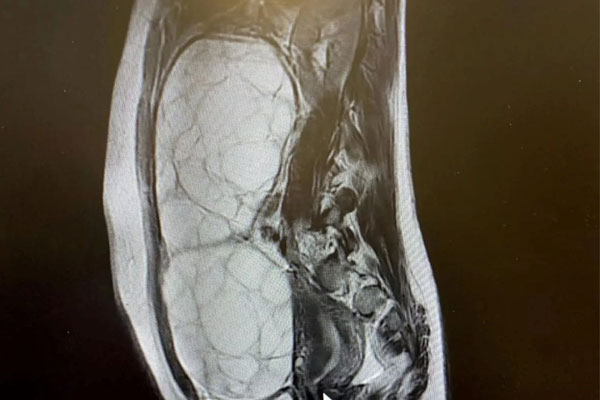

Alex lần đầu tiên nhận thấy các triệu chứng khó chịu trong một chuyến du lịch cùng gia đình và khi về nhà, cô đã nhanh chóng đặt lịch hẹn kiểm tra sức khỏe với bác sĩ. Cô đã được xét nghiệm máu và chỉ một tuần sau, được đưa đến bệnh viện để siêu âm. Vào thời điểm này, cô đã mất thị lực ngoại vi ở mắt trái và được thông báo rằng buồng trứng của cô đã phát triển thêm 13 cm.

Các xét nghiệm tiếp theo cho thấy Alex có một khối u tuyến yên hiếm gặp, cả thế giới mới chỉ ghi nhận tổng cộng 20 trường hợp tương tự và cô chỉ cách cái chết 1 tuần. "Khi mới 16 tuổi, cuộc sống của tôi vụt qua trước mắt. Những gì tôi thực sự quan tâm, không còn ý nghĩa gì với tôi kể từ ngày đó", nữ sinh tiết lộ cô được chỉ định phải phẫu thuật gấp trước khi khối u vỡ ra và gây nguy hiểm đến tính mạng.

Sau cơn khủng hoảng, Alex được chẩn đoán mắc hội chứng PTSD (rối loạn căng thẳng sau sang chấn). Cô gần như đã bỏ lỡ cả một năm học, bao gồm cả kỳ thi, do quá trình hồi phục kéo dài. 13 tháng sau, Alex được thông báo rằng cô cần phẫu thuật khẩn cấp sau khi khối u đã phát triển và đè lên dây thần kinh thị giác của cô.

Vào tháng 2/2023, cô đã trải qua liệu pháp chùm tia proton, một phương pháp xạ trị có mục tiêu và ít xâm lấn hơn trong 5 tuần. Đến tháng 12 cùng năm, thêm nhiều tin xấu nữa đến khi Alex được thông báo rằng xạ trị không thành công và cô gái cần phải phẫu thuật lần thứ ba. Cuộc phẫu thuật diễn ra thành công nhưng Alex vẫn đang được điều trị để loại bỏ hoàn toàn khối u ác tính này.